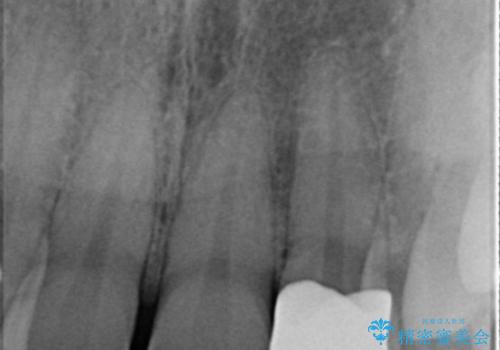

- 左の前歯が黒いとのことで来院。

1番目の歯は小さい虫歯があったのでプラスチックの樹脂で治療をしました(保険内)。

2番目の歯は二箇所虫歯があり、プラスチックの樹脂で治療するとつぎはぎみたいになってしまうので、

白い被せ物(ジルコニアクラウン)で治療しました。